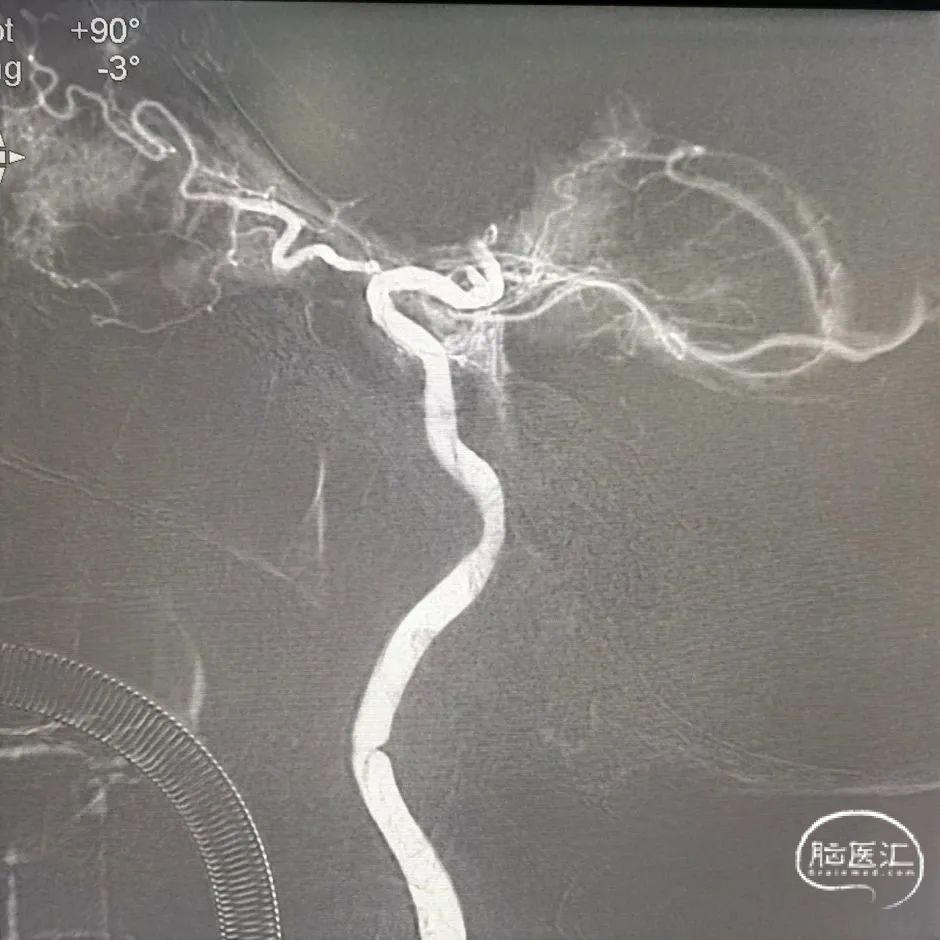

通过中间导管将保护伞到位,退出中间导管,长鞘退至颈总动脉,4.5*30mm 球囊扩张颈内动脉狭窄段,球扩后满意,释放7*40mm 支架。

术后正侧位造影:全程血流恢复满意。

本例手术考虑颈动脉夹层,颈动脉慢性狭窄急性闭塞,术中使用泥鳅导丝+125多功能导管突破后立即使用6F 115cm中间导管于颈内动脉抽吸,2次均抽出血栓,但6F中间导管通过性有限,很难到达眼段以上水平。

在大脑中动脉取栓过程中,Syphonet®取栓支架血栓抓取能力表现良好。